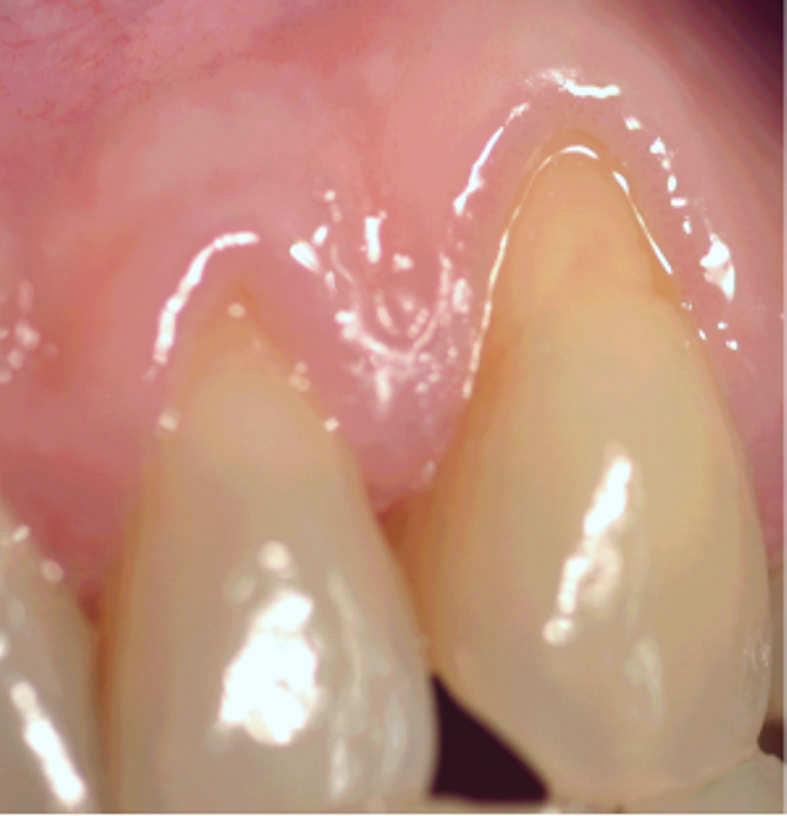

Mucogingival Therapy as "non surgical and surgical correction of the defects in morphology, position and/or amount of soft tissue and underlying bone". This assigns importance to non-surgical therapy and to the bone condition because of its influence on the morphology of the defects. In this respect the Mucogingival Therapy includes: Root coverage procedures, Gingival augmentation, Augmentation of the edentulous ridge, Removing of the aberrant frenulum, Prevention of ridge collapse associated with tooth extraction, Crown lengthening, Teeth that are not likely to erupt, Loss of interdental papilla which presents an aesthetic and/or phonetic problem.